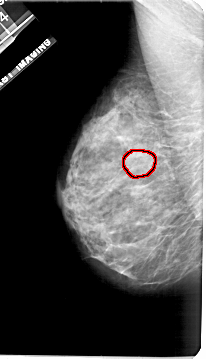

FILE: A_1921_1.LEFT_CC.OVERLAY

TOTAL_ABNORMALITIES 1

ABNORMALITY 1

LESION_TYPE MASS SHAPE OVAL MARGINS OBSCURED

ASSESSMENT 3

SUBTLETY 2

PATHOLOGY BENIGN

TOTAL_OUTLINES 1

BOUNDARY